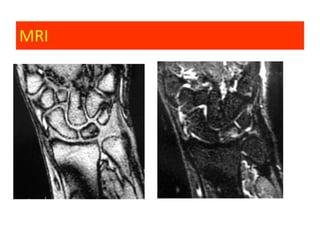

Ulnocarpal Impaction Syndrome

Clinical features:

• Ulnar sided wrist pain

• Associated degenerative changes:

–   Ulnar side of the lunate

–   Radial side of the ulnar dome

–   TFCC central tear

–   Triquetrum- LunoTriquetrum lig.

• Usually positive or neutral ulnar variance

MRI